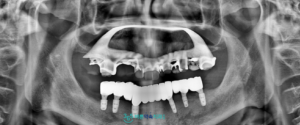

모든 치료가 마무리된 후의

구강 내 사진과 파노라마 사진입니다.

전 < 후